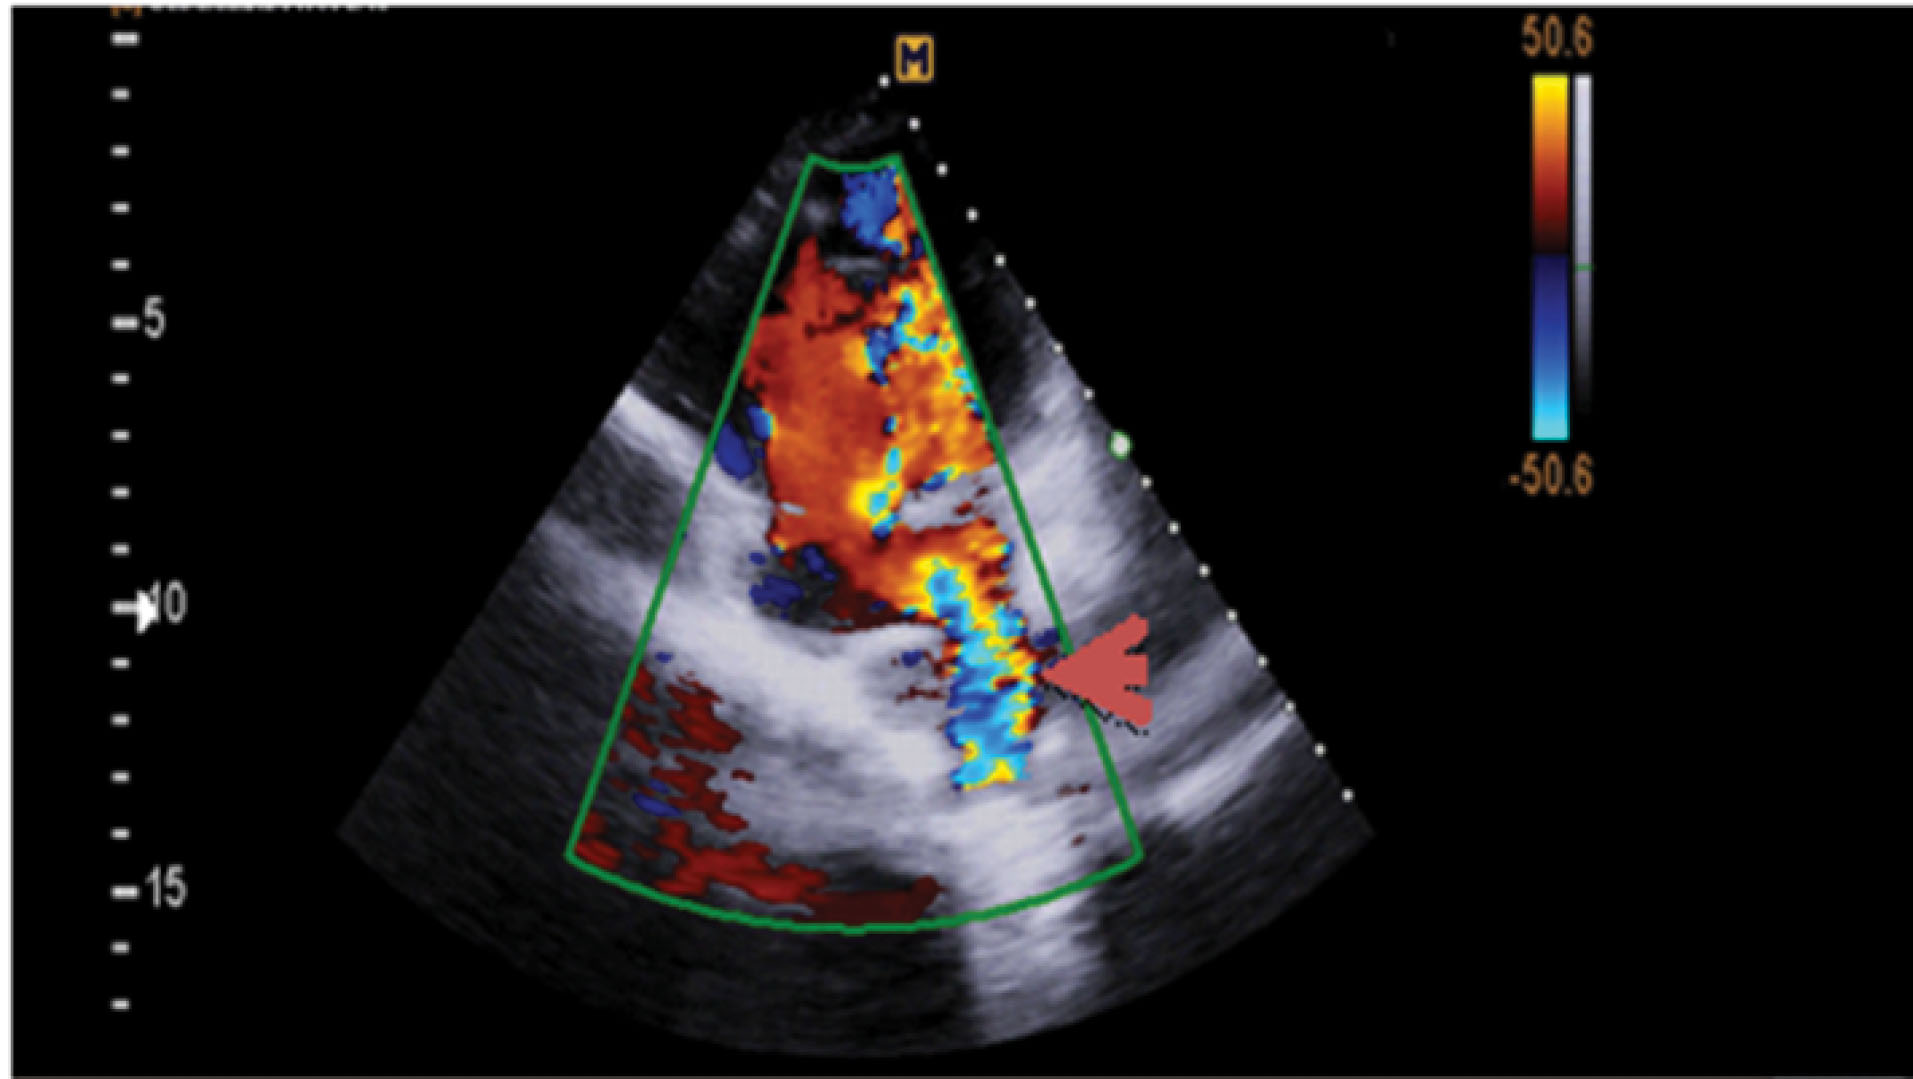

Hemoglobin concentration was 17g/dL. Electrocardiogram showed low voltage, poor R progression and left anterior hemiblock. Contrast trans-thoracic echocardiography (TTE) with an injection of agitated saline from left brachial vein showed a left-sided dilated para-aortic vessel including a blue color descending flow suggested left superior vena cava (LSVC) with a fast entrance of bubbles into the left atrium (). Finally, she underwent cardiac magnetic resonance imaging (CMR) due to cyanosis which revealed the presence of very engorged dilated left lower and left upper pulmonary veins with fistulous connection which left upper pulmonary vein (LUPV) connected to vertical vein and then into an innominate vein and finally SVC. The direction of flow was from SVC to left upper pulmonary vein, left lower pulmonary vein, and left atrium (LA). (). This Fistula was seen as collateral vessels connected proximally to the inferior aspect of innominate vein and distally to the left lower pulmonary vein. There were some connections between the ascending, and descending limbs of these tortuous venous collaterals and these direct connections between venous collateral vessels could explain fast pass of agitated saline into LA during TTE with contrast study and severe cyanosis of the patient. Probably this abnormal connection of LUPV to vertical vein (PAPVC) was not diagnosed before Fontan operation and developed gradually due to the pressure gradient in the Fontan circuit with connection to LLPV. This pressure gradient could result in further dilatation of vertical vein and prominence of collateral vessels which were connected to the inferior aspect of innominate vein. Thus, catheterization was performed () and Femoral vein was cannulated. We passed from IVC to fontan circuit, SVC, innominate and lastly vertical vein. In injection in vertical vein, we found severe engorged and tortoise pulmonary veins, then a long stiff exchange wire (260 cm) with a long LIFETECH delivery sheath 9F passed through fontan circuit to SVC, innominate vein and vertical vein. An ADO device 14*16 mm chosen and deployed at proximal of vertical vein (). After the detachment of device by vertical injection we confirmed proper position of device and small residual flow. The oxygen saturation immediately increased from 80% to 93%. In the first echocardiography performed after device closure, some contrast agents were entered into the left atrium through a right to left shunt, which indicates the presence of a residual shunt. This might be due to the delayed endothelialization of implanted device.

jcvtr-13-364-g001

Figure 1. Color doppler flow in trans- thoracic echocardiography shows turbulent flow from left inferior pulmonary vein into left atrium (red arrow)